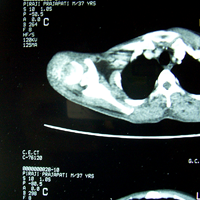

Case:6 Transfer of Scapula to Humerus

Angio-2

Angiogram

Pre-op CTscan

Pre-Op X-ray